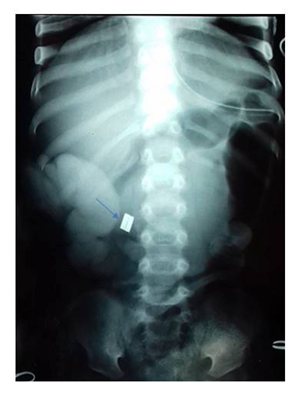

An 18-months-old- child was admitted for febrile occlusion evolving for 48 hours. The physical examination revealed a fever at 38°C, dehydration stage II and a distended with sensitive abdomen. Radiography showed metallic sphere of 5millimetersin the upper abdomen without pneumoperitoneum flank (Figure 1). After conditioning and ressisutation, a transverse laparotomy revealed generalized peritonitis with two perforations of the hail at 600 and 800millimeters from the Treitz angle (Figure 2). It was related to a necrosis of the intestinal wall between two magnets. A peritoneal toilet with a terminal ileostomy was made. The clinical evolution was favorable. Closure of the stoma was performed after one month and follow-up is about 3years.